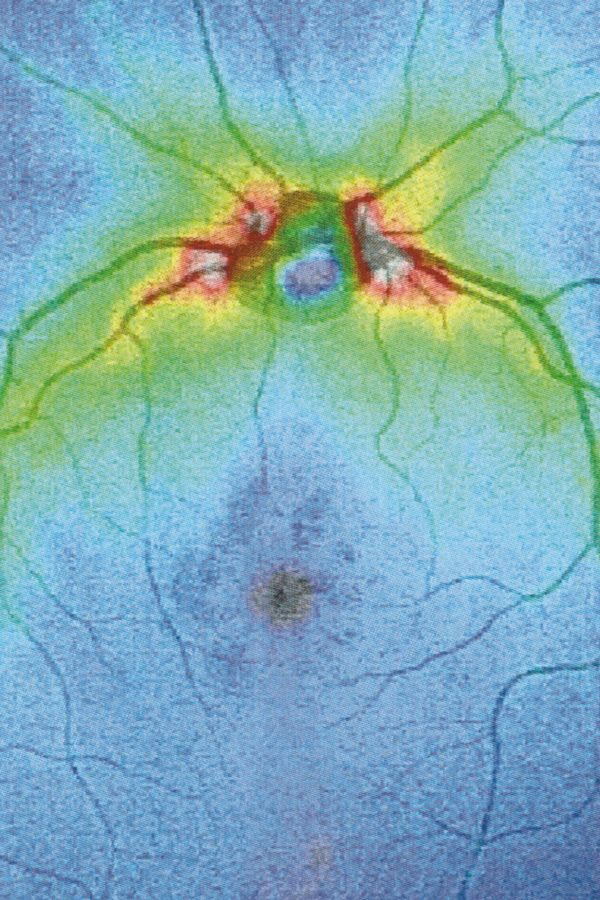

Collirio (Eyewash) is the attempt to demonstrate the non-absoluteness of visual experience and its nature as a situated and yet ambiguous act. It is the path that has allowed me to understand how my fears do not have roots in an unknowable place. The eye is not an unfathomable globe.